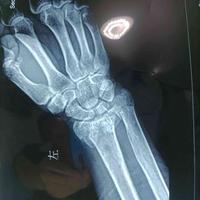

何为正,何为反?复位固定满意才是你收工的

何为正,何为反?复位固定满意才是你收工的标准。...